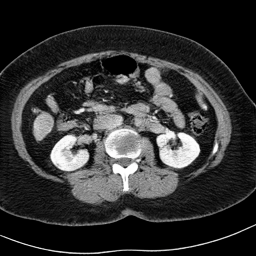

In many clinical settings, the use of both Computed Tomography (CT) and Magnetic Resonance (MRI) is necessary to pursue a thorough understanding of the patient's anatomy and to plan a suitable therapeutical strategy; this is often the case in MRI-based radiotherapy, where CT is always necessary to prepare the dose delivery, as it provides the essential information about the radiation absorption properties of the tissues. Sometimes, MRI is preferred to contour the target volumes. However, this approach is often not the most efficient, as it is more expensive, time-consuming and, most importantly, stressful for the patients. To overcome this issue, in this work, we analyse the capabilities of different configurations of Deep Learning models to generate synthetic CT scans from MRI, leveraging the power of Generative Adversarial Networks (GANs) and, in particular, the CycleGAN architecture, capable of working in an unsupervised manner and without paired images, which were not available. Several CycleGAN models were trained unsupervised to generate CT scans from different MRI modalities with and without contrast agents. To overcome the problem of not having a ground truth, distribution-based metrics were used to assess the model's performance quantitatively, together with a qualitative evaluation where physicians were asked to differentiate between real and synthetic images to understand how realistic the generated images were. The results show how, depending on the input modalities, the models can have very different performances; however, models with the best quantitative results, according to the distribution-based metrics used, can generate very difficult images to distinguish from the real ones, even for physicians, demonstrating the approach's potential.